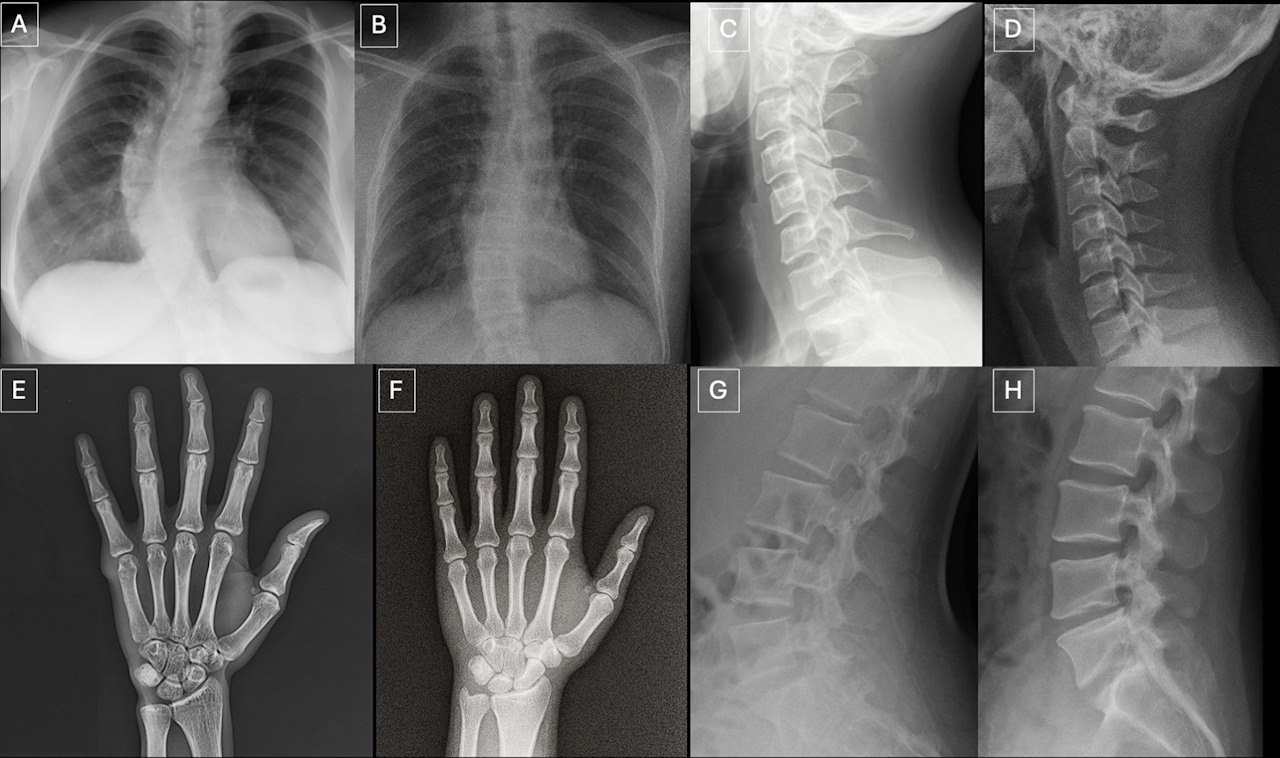

Пари зображень, які показували радіологам. У кожній парі зображення зліва справжнє, а зображення справа — згенероване  GPT-4o. Tordjman et al. / Radiology, 2026

Лікарі з більшим досвідом роботи загалом дещо точніше розпізнавали фейки, а гірший результат отримали спеціалісти, які витратили більше часу на опис зображення. Серед ознак, що допомогли відрізнити справжні зображення від штучних, лікарі називали надмірну «ідеальність»: на згенерованих зображеннях сторонні шуми були більш рівномірними, а хребці, легені та галуження судин — більш симетричними, краї зламаних кісток здавалися акуратнішими, краї ребер — рівнішими. Серед моделей штучного інтелекту GPT-4o найкраще шукав фейкові зображення — з точністю 85 відсотків, тоді як успішність Llama 4 Maverick ледь перевищила поріг випадкового вгадування із результатом у 51,8 відсотка.